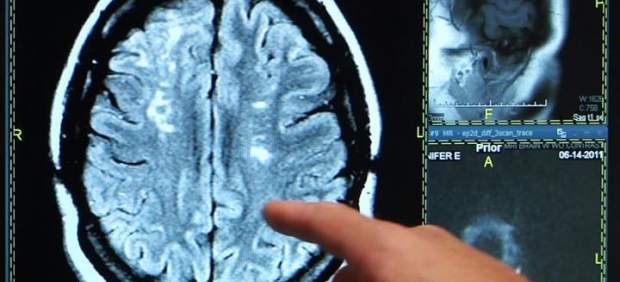

En el ictus, el tiempo es cerebro; cada minuto que pasa cuenta porque desde que aparecen los síntomas se pierden miles de neuronas que se pueden salvar si se aplican lo antes posible medidas de tratamiento adecuadas, pero antes de llegar a esta situación el 90 % de ellos se puede prevenir.

Los síntomas que hay que saber reconocer y deben hacer pensar en un ictus, según ha señalado en rueda de prensa la coordinadora del Grupo de Estudio de Enfermedades Cerebrovasculares de la Sociedad Española de Neurología (SEN), María Alonso, aparecen casi todos «de una forma muy brusca, no avisan».